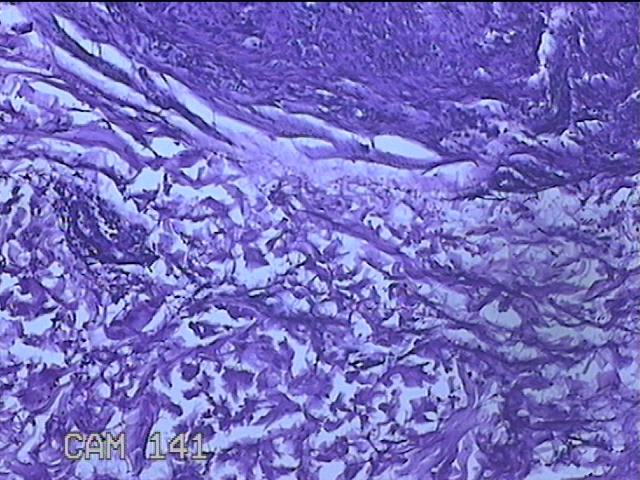

左侧臀部结节

性别

男

年龄

40岁

临床诊断

皮下结节

一般病史

发现左侧臀部结节1年余。

标本名称

大体所见

灰白粉红色组织1.3x0.8x0.3cm一块,表面带梭形皮肤1.3x0.8cm,皮下见结节1.3x1x0.7cm一个,切开结节呈实性,切面灰白粉红色,质软。

图2